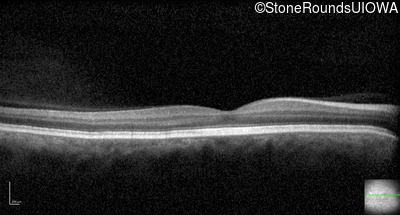

Optical Coherence Tomography - Right - 20/160 -1

Exemplar / OCT Stack